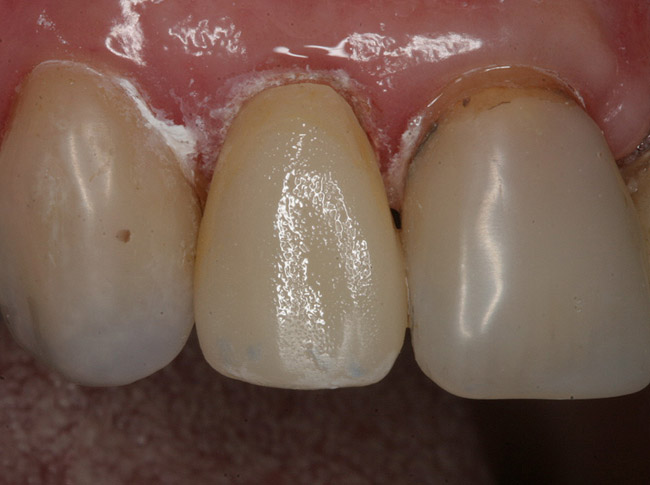

At the insertion appointment, the temporary is removed and the bonding surfaces of the preparation are lightly cleaned with a micro-abrasion unit. The cementation surface is reactivated with one coat of adhesive, air-thinned, and light-polymerized (Figure 7). The restoration is then placed with a dual-cure resin cement and light-polymerized (Figure 8 and Figure 9).

Figure 8  The restoration was then placed with a dual-cure resin cement and light-polymerized.

Figure 8

Figure 9  The restoration was then placed with a dual-cure resin cement and light-polymerized.

Figure 9